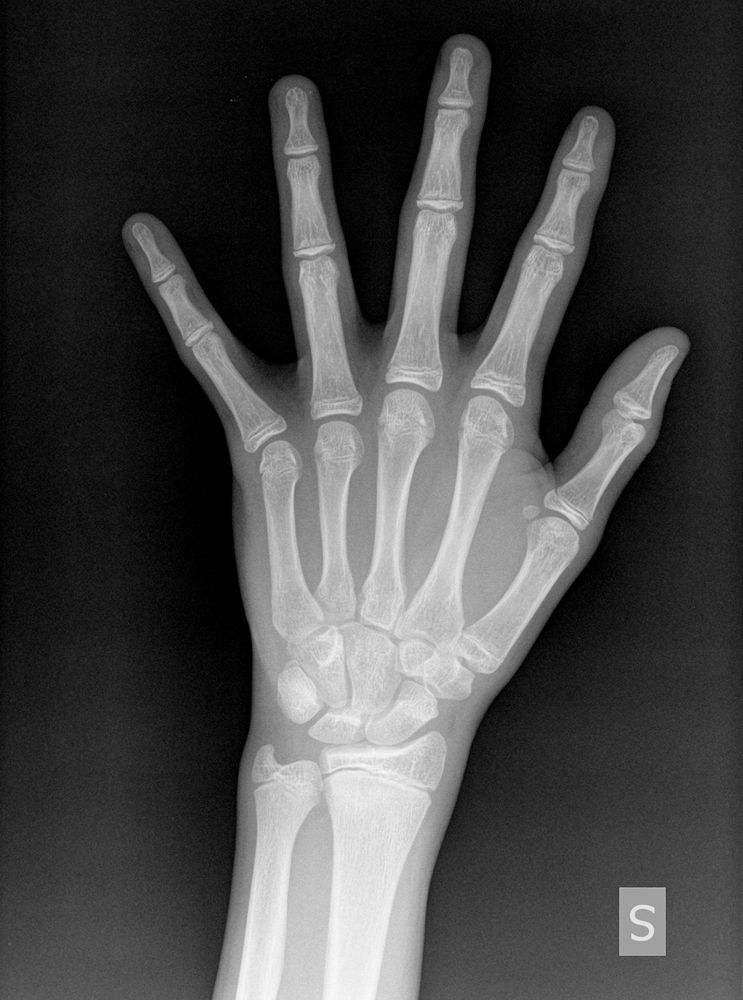

THE HAND RADIOGRAPH

The hand radiograph is asked to assess bone age and this ca be estimated with a six-month margin of error. The most commonly used reference standard is the atlas published by Gruelich and Pyle which analyses not only growth plates but also the form and dimension of phalangeal and carpal bones.

The hand radiograph is a precious tool when deciding whether or not starting any kind of treatment and whether or not asking a radiography of the spine in case reliable data about growth velocity curve should lack and in case of conflicting data about the developmental phase such as lower-than-normal growth velocity or menarche absence.